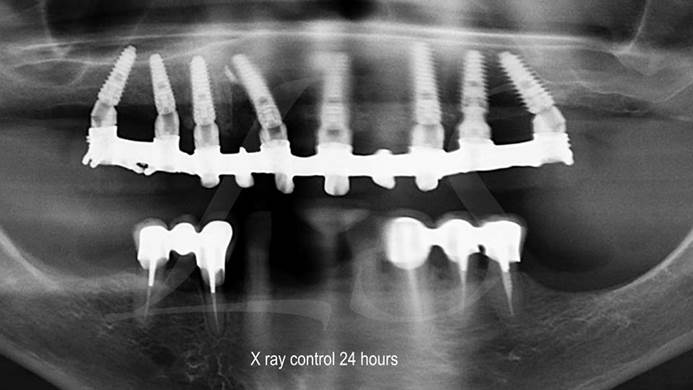

Clinical case: Full-arch implant treatment with immediate loading & extraction implantation

- Courtesy of Dr. Laurent Sers, France -

AnyRidge, R2GATE, guided surgery, Dr. Laurent Sers, immediate loading, maxilla

AnyRidge implant system, R2GATE, Digital prosthesis

“Patient’s smile was recovered on the day of surgery

with reliable & highly-aesthetic results using AnyRidge & R2GATE. ”